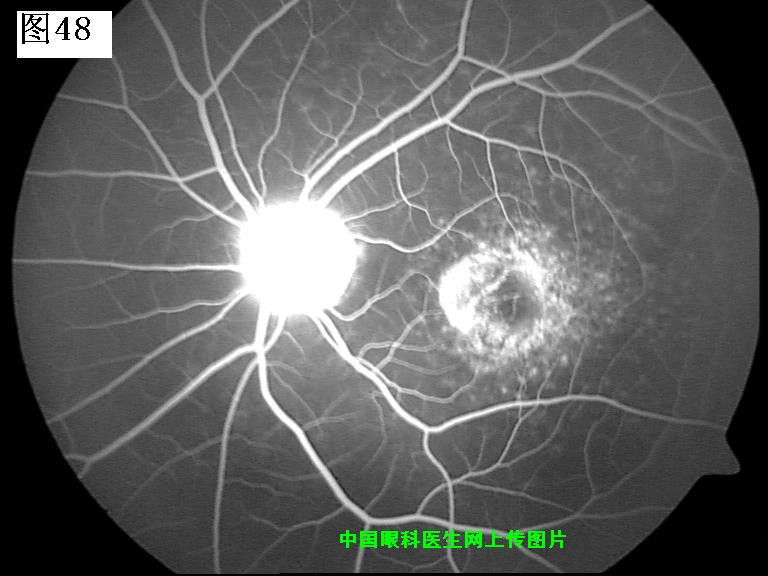

45 46 47 48